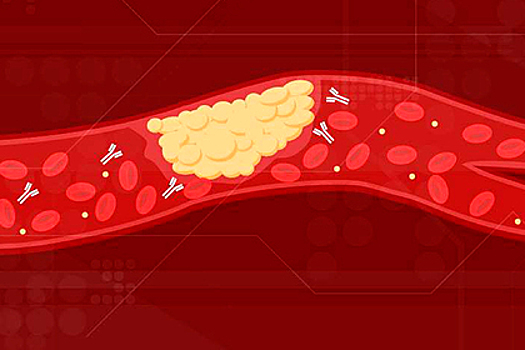

Оказалось, что COVID-19 может спровоцировать появление аутоиммунных тел, которые циркулируют в крови, атакуют клетки и вызывают образованием тромбов в артериях, венах и микроскопических сосудах.

Тромбы могут привести к инсультам, а также ограничить кровоток, снижая доступ клеткам к кислороду. Подобные аутоиммунные тела наблюдается не только у пациентов с COVID-19, но также у людей с аутоиммунным заболеванием, называемым антифосфолипидным синдромом.

Исследователи выяснили, что около половины пациентов с тяжелыми симптомами COVID-19 демонстрировало высокие уровни опасных антител и суперактивных нейтрофилов — белых кровяных телец, участвующих в нетозе. Утверждается также, что при нетозе нейтрофилы погибают, выбрасывая нити ДНК и, тем самым, уничтожая различные патогены.